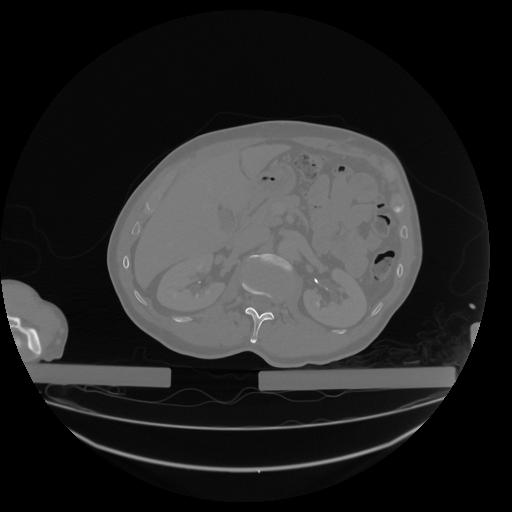

34 CUERPO,CE,Vol,1.0,CUERPO,,